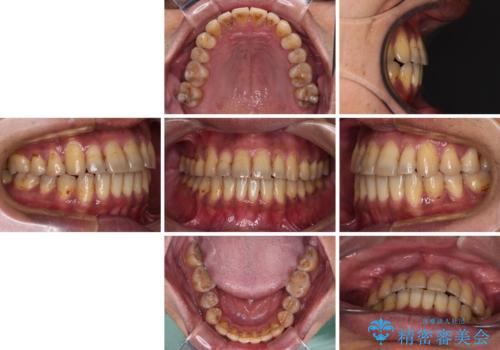

前歯のクロスバイトを改善 ワイヤー装置での非抜歯矯正

上下の叢生は速やかに改善できましたが、右側のクロスバイトの改善に1年以上の期間を要しました。

- 2年5ヶ月

- 10-30回